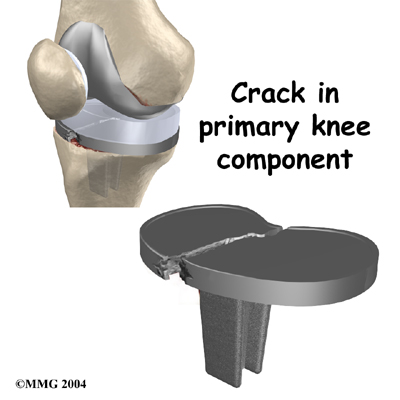

Breakage

Finally, the metal of the artificial joint can due to the constant stress that the artificial joint undergoes everyday. In weight-bearing joints like the knee, this is greatly affected by how much you weigh and how active you are.